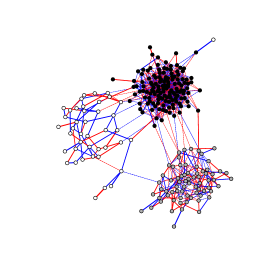

5.2 Breast Cancer data

We tested our algorithm on a gene expression data set provided by Hess et al. (2006) and concerning patients with stage breast cancer. The patients were treated with chemotherapy prior to surgery. Patient response to the treatment is classified as either a pathologic complete response (pCR) or a residual disease (not-pCR). Hess et al. (2006) and Natowicz et al. (2008) developed and tested a multigene predictor for treatment response on this data set. They focused on a set of 26 genes having a high predictive value (see Table 1). We thus consider a total of cases containing gene expression levels.

When dealing with gene regulatory networks, we typically observe

independent microarray experiments, each giving the expression

levels of the same genes. If the same experimental conditions

are used for all microarrays, these may be considered as a sample of

the same experiment. In the application in question, cases from the

pCR class (34 cases) and from the not-pCR class (99 cases) clearly do

not have the same distribution. We apply our algorithm on each

class of patients. Two distinct gene regulatory networks are thus

inferred.

Figure 3 plots the resulting networks obtained for three different penalizations. The penalization parameters were heuristically chosen from the number of expected nonzero entries. We used latent clusters, and it is interesting to note that when assuming more than two clusters, the algorithm systematically produces exactly two non-empty clusters.

The inferred networks exhibit very different structures according to the class of patients. This in itself is interesting and suggests that gene regulation differs with respect to the presence or absence of a pCR.

The network obtained with not-pCR cases displays a two-star pattern. Each star connects to a unique gene, either SCUBE2 or IGFBP4. Almost all the most significant connections imply SCUBE2. This star pattern suggests that further studies of this particular gene would be of interest for understanding residual disease.

The network estimated with the pCR cases has a different two-cluster structure. In particular, it groups IGFBP4 and SCUBE2 in the same cluster with a direct significant link. This again indicates a completely different relationship between the genes in pCR versus non-pCR.